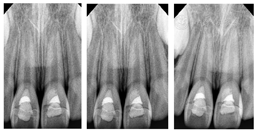

2周后复诊:11、21断牙粘接稳固,松动I度,牙龈无红肿,根尖区扪诊无不适。咬合时近中舌侧有早接触,早接触点位于舌侧近远中边缘嵴近颈缘部分,牙齿松动度无明显改善,当日进行调牙合治疗,调磨方式采用选磨法,选择对牙合牙近切端的唇斜面及患牙近远中边缘嵴调牙合。X线根尖片(图3)显示:11、21牙周膜均匀,根尖周未见低密度破坏影像。

5个月后随访:11、21断冠粘结稳固,边缘密合,叩痛(-),无松动,唇腭侧牙龈无异常。X线根尖片显示(图4):11、21牙根较之前明显延长,根尖孔接近闭合,未见低密度影像。

2年后随访(图5):11、21无松动,断冠粘接稳固,菌斑性牙龈炎。X线根尖片显示:11、21根管口可见高密度钙化桥形成,11、21牙根发育完成,根尖周未见异常,牙根长度较健康邻牙无差异。